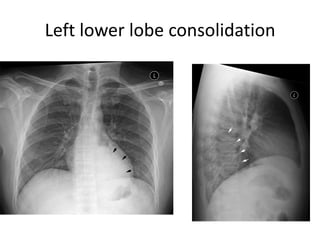

Left lower lobe consolidation

Left lower lobeconsolidation